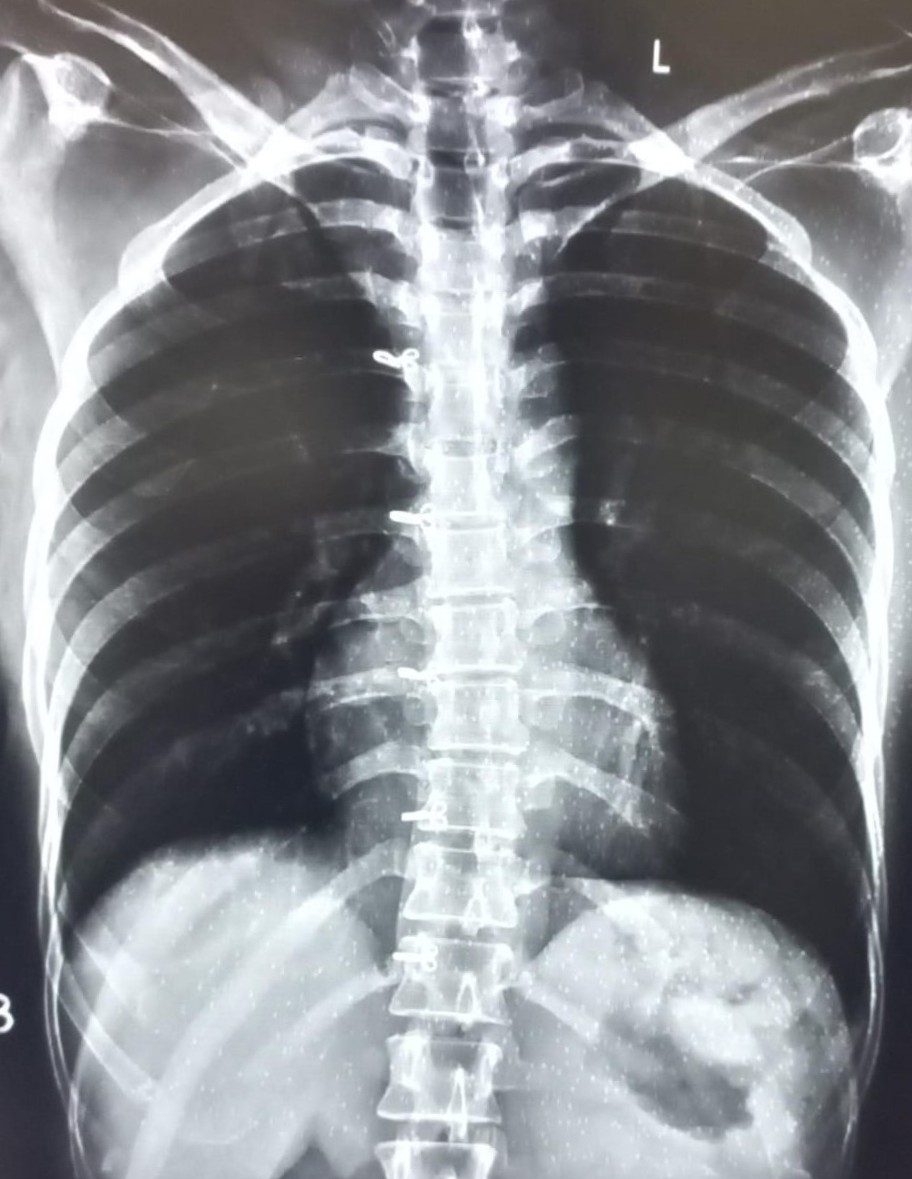

| 4440 | IGGMC, Nagpur, Nagpur | P2 | 29-32 | kamal dasar | Consent taken on Paper | 49 Yrs. |

Provisional Diag : cough under evaluation

Final Diag : OBLITERATION OF LEFT CP ANGLE BLUNTING/LEFT SIDED PLEURAL EFFUSION |

Non-TB Case (Confirmed) | OBLITERATION OF LEFT CP ANGLE BLUNTING/LEFT SIDED PLEURAL EFFUSION | Abnormality visible on x-ray |